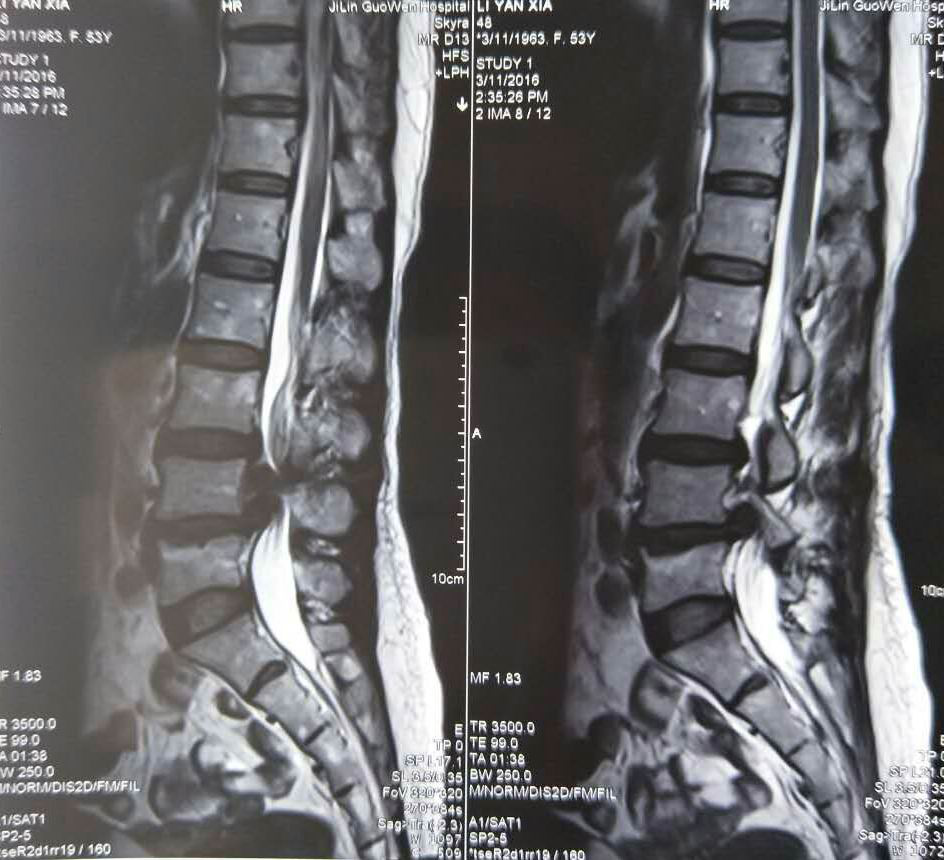

術(shù)前腰椎核磁檢查有助于診斷及確定手術(shù)方案